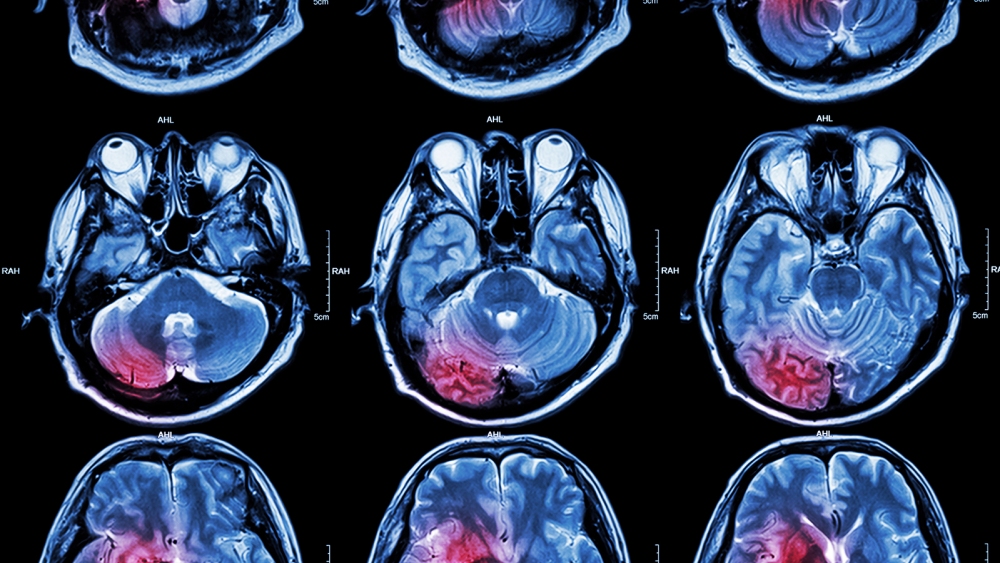

The world’s top killer: Cholesterol is a waxy substance made by our livers and found in certain foods. It comes in two forms, HDL and LDL, and while having high levels of HDL cholesterol in your blood appears beneficial, high levels of LDL cholesterol will eventually block your arteries, leading to cardiovascular disease, heart attacks, and strokes.

This kind of heart disease is the number one cause of death in the U.S. and around the world, and even non-fatal heart attacks and strokes can cause severe pain and disability for millions of others.